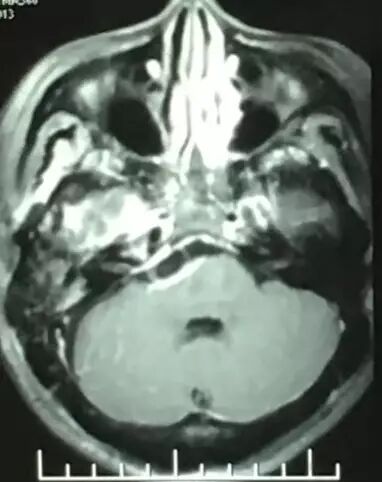

术后MRI T2加权像

术后MRI T1平扫,复查可见明胶海绵影(高信号)。